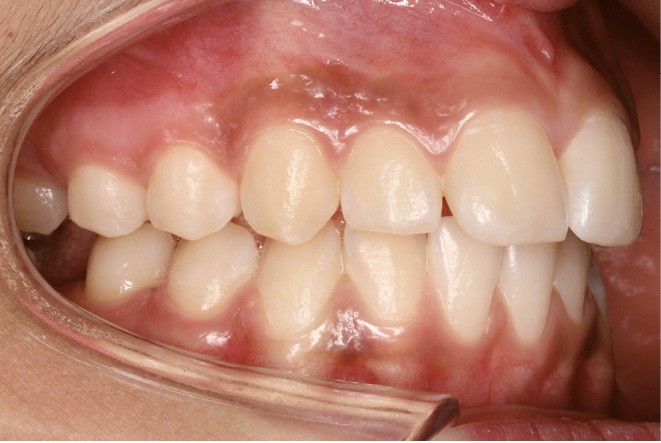

Examen endobuccal (fig. 2a-e)

L’hygiène est satisfaisante et le parodonte sain. On note aux deux arcades l’absence des premières molaires et la fermeture partielle des espaces d’extraction avec mésiorotation marquée de 17, 27 et 37. À la mandibule, l’encombrement antérieur est estimé à 2 mm et les espaces d’extraction résiduels à 12 mm.

Dans le sens transversal, malgré une occlusion correcte des secteurs latéraux, on observe une endoalvéolie maxillaire et une non-concordance des médianes incisives avec déviation de la médiane mandibulaire vers la droite. Le recouvrement incisif est normal.